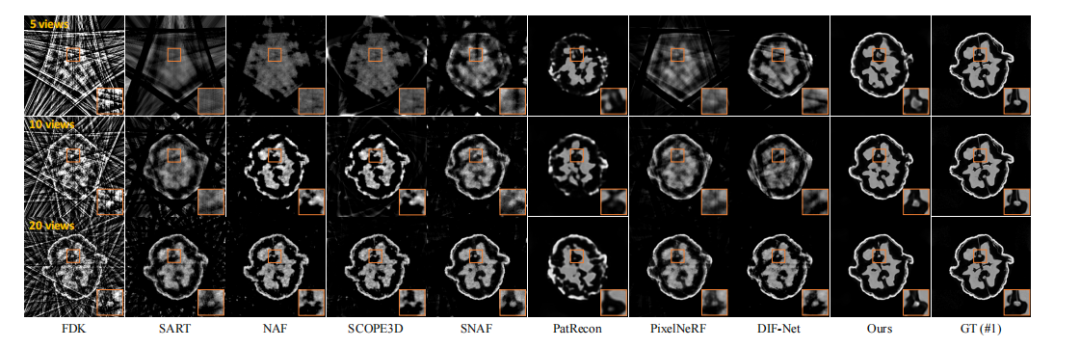

parison of 3D CBCT images reconstructed in axial slices fromcase #10 of dental dataset. It is evident that the FDK approach struggles with sparse-view input, leading to significantstreaky artifacts because of the limited number of input views.Although SART reduces these artifacts, it often loses finedetails in the process. When it comes to neural renderingbased methods, NAF achieves decent results with 20 viewsby incorporating neural rendering with hash encoding. Yet,its performance greatly diminishes with very few input views(such as 5 or 10), as it is optimized for individual objectsand lacks prior knowledge learned from the data population.SCOPE3D shows similar performance, as the re-projectionstrategy offers negligible new information. SNAF demonsratesimprovements due to its view augmentation strategy but stillstruggles with 10 or 5 views. PatRecon ignores geometricrelationships among multi-view projections, which results inblurry reconstructions with erroneous structures. Benefitingfrom CNN layers, PixelNeRF enjoys prior knowledge andmaintains multi-view consistency. But it tends to producenoticeable streaky artifacts due to its point-wise MLP decodingand 2D supervision. DIF-Net builds upon the principles ofPixelNeRF, achieving better results due to its 3D supervision.The results with 20 views input are comparable to ours,with slight blurriness and noise as highlighted in the orangebox. However, its performance degrades with sparser inputs,such as 5 views, exhibiting streaky artifacts due to its pointwise MLP decoding approach. This is because the point-wiseMLP independently decodes the attenuation of each querypoint, disregarding the spatial relationships among neighboringvoxel points in CBCT image. MLP decoder is also unable tocapture the global structure information of CBCT image withthe point-wise 3D supervision. As a result, it would deliverstreaky artifacts, especially when facing extremely sparse inputlike 5 views. In contrast, our CNN-based decoding moduleconsiders interactions among neighboring points, effectivelyacting as a learnable filter to mitigate noise and extract morerobust feature representations. Moreover, 3D CNN decoder iscapable of capturing the global structure information with thevolume-wise 3D supervision. Consequently, our reconstructedCBCT images exhibit higher quality with less streaky artifacts.Notably, our approach surpasses all other methods, providingreconstruction quality comparable to the ground truth with 20input views. However, recovering details with high fidelitybecomes challenging for our method when facing 10 or 5views. Despite this limitation, our method still maintains aclear advantage over the competition, showing less streakyartifacts and preserving a better global structure.

图 5 展示了来自牙科数据集第 10 号病例的 3D CBCT 图像在轴向切片中的并排比较。显然,FDK 方法在稀疏视角输入下效果较差,因输入视角数量有限导致显著的条纹伪影。虽然 SART 方法能够减少这些伪影,但在处理过程中常常会丢失细节。对于基于神经渲染的方法,NAF 在 20 个视角的情况下通过将神经渲染与哈希编码结合,达到了较好的效果。然而,当输入视角非常少(例如 5 或 10 个)时,其性能急剧下降,因为它是针对单个物体优化的,且缺乏从数据集群体中学习的先验知识。SCOPE3D 表现相似,因为其重新投影策略带来的新信息微乎其微。SNAF 通过视角增强策略有所改善,但在 10 个或 5 个视角时仍然表现不佳。PatRecon 忽视了多视角投影之间的几何关系,导致重建图像模糊,结构错误。借助 CNN 层,PixelNeRF 利用了先验知识,保持了多视角一致性,但由于其点式 MLP 解码和 2D 监督,它会产生明显的条纹伪影。DIF-Net 基于 PixelNeRF 的原理进行改进,得到了更好的结果,因为它具有 3D 监督。20 个视角输入下的结果与我们的结果相当,稍微有一些模糊和噪声(如橙色框中所示)。然而,当输入视角更稀疏(如 5 个视角)时,其性能下降,出现条纹伪影,原因在于其点式 MLP 解码方法。点式 MLP 独立解码每个查询点的衰减,忽略了 CBCT 图像中相邻体素点之间的空间关系。MLP 解码器也无法捕捉 CBCT 图像的全局结构信息,因此会产生条纹伪影,尤其是在输入视角极其稀疏(如 5 个视角)时。相比之下,我们基于 CNN 的解码模块考虑了相邻点之间的相互作用,能够有效地作为可学习的滤波器来减轻噪声,并提取更强健的特征表示。此外,3D CNN 解码器能够通过体积级 3D 监督捕捉全局结构信息。因此,我们重建的 CBCT 图像具有更高的质量,条纹伪影较少。值得注意的是,我们的方法在所有其他方法中表现最佳,且在 20 个输入视角下的重建质量与真实图像相当。然而,当面对 10 或 5 个视角时,我们的方法在恢复高保真细节时面临挑战。尽管如此,我们的方法仍然保持了相对于其他方法的明显优势,条纹伪影较少,并且保留了更好的全局结构。

Fig. 5. A qualitative assessment of case #10 within the dental dataset (a section taken along the axial plane). Window settings: [-1, 2] thousand Hounsfield units (HU).

图5:牙科数据集案例#10的定性比较(轴向切片)。窗宽:[-1000, 2000] HU。